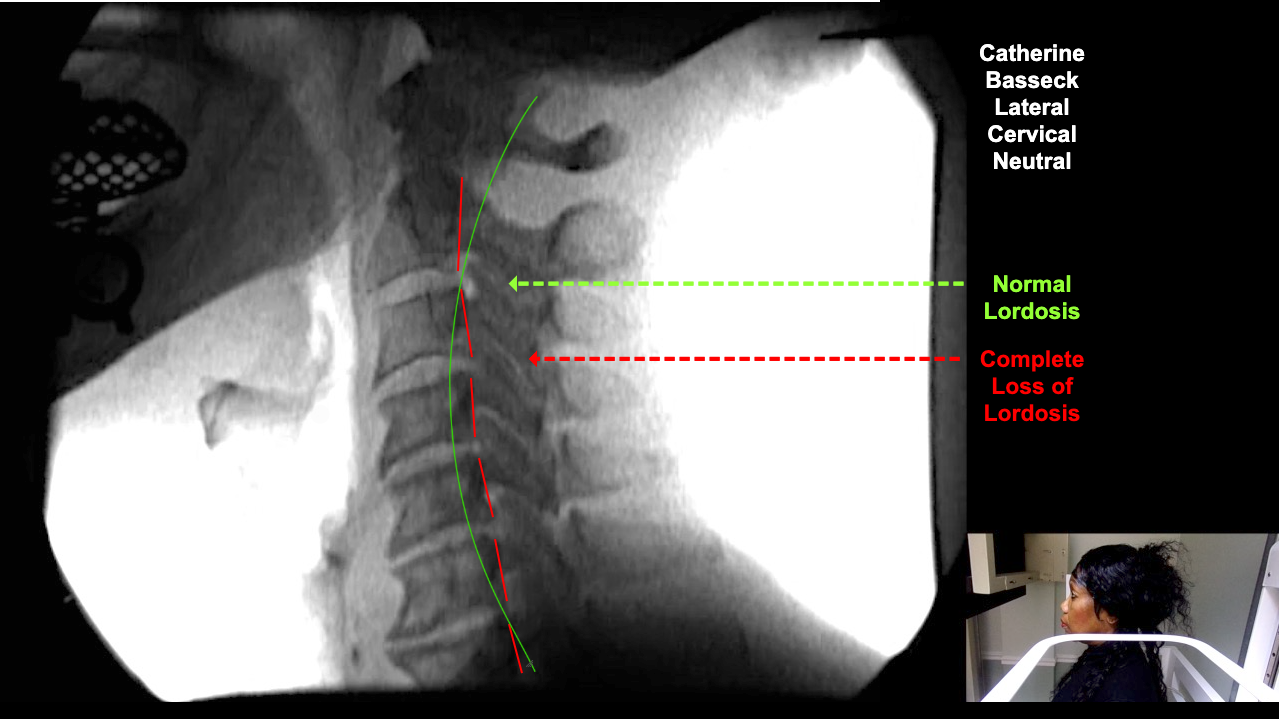

Home > Catherine Basseck 10-23-25